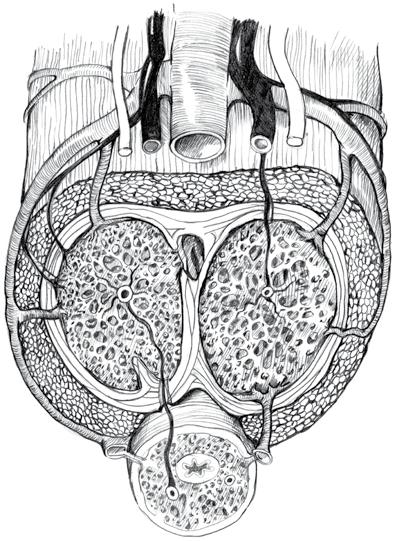

3. Anatomie a fyziologie mužského genitálu 43

3.1 Anatomie .............................................................. 43

3.1.1 Zevní pohlavní orgány 43

3.1.2 Vnitřní pohlavní orgány ........................ 45